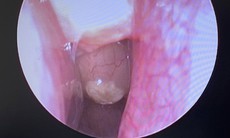

Hình ảnh phim phổi cho thấy tổn thương lan tỏa kín hai bên, hình ảnh kính mờ điển hình của cúm, nhanh chóng chuyển sang Hội chứng Suy hô hấp cấp (ARDS) – biến chứng nặng thường gặp ở người suy giảm miễn dịch.